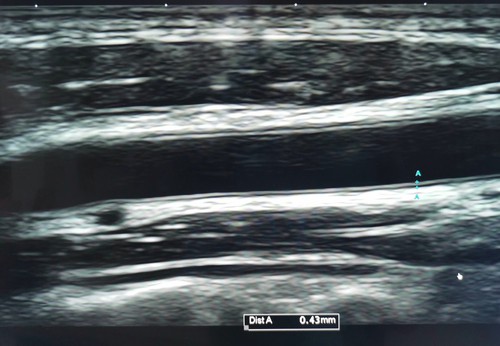

Tes lainnya, mis. MRI jantung, tes ketebalan intima-media karotis

Hal ini juga dapat mencakup pemantauan tekanan darah yang lebih lama untuk menilai pola tekanan darah sepanjang hari, atau USG arteri karotis untuk menilai risiko stroke.

- Uji Ketebalan Intima-Media Karotis